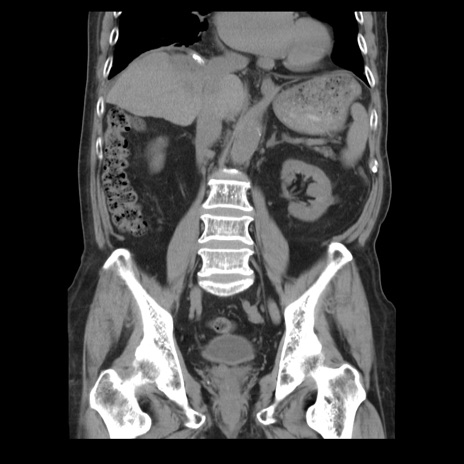

症例21(冠状断像)

【症例】70歳代男性

【主訴】腹痛

【現病歴】肝硬変・肝細胞癌にてかかりつけの方。約9時間前に食後より腹痛出現。症状が徐々に増悪し、嘔吐出現したため来院。

【既往歴】肝硬変、肝細胞癌(RFA、TACE後)

【身体所見】意識清明、表情苦悶様、BT 36℃、BP 129/78mmHg、P 88bpm、SpO2 97%(RA)、右上腹部から心窩部にかけて圧痛あり、反跳痛なし、筋性防御あり。

【データ】WBC 5800、CRP 0.16